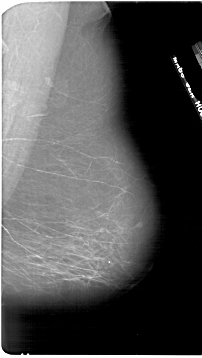

A_1849_1.RIGHT_MLO

RIGHT_CC LINES 6646 PIXELS_PER_LINE 3706 BITS_PER_PIXEL 12 RESOLUTION 43.5 NON_OVERLAY

RIGHT_MLO LINES 6796 PIXELS_PER_LINE 3826 BITS_PER_PIXEL 12 RESOLUTION 43.5 NON_OVERLAY